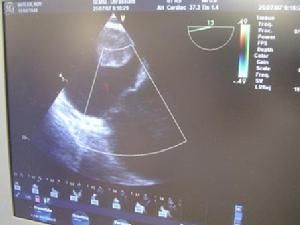

1、右心房粘液瘤,當腫瘤阻塞瓣孔時,亦可引起三尖瓣狹窄的臨床表現,但病史短,病程進展迅速,超聲心動圖有獨特的雲霧狀圖像,可資鑑別。